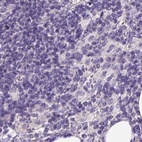

Immunohistochemistry analysis in human pancreas and colon tissues using Anti-PDIA2 antibody. Corresponding PDIA2 RNA-seq data are presented for the same tissues.